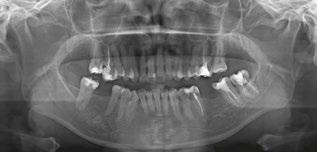

Patient S.T., age 32, presented in the hope of creating a radiant smile and a functional bite. She had been dealing with dental problems all her life. Her X-rays exhibited multiple direct restorations as well as endodontic treatment. Due to the loss of her molars, her teeth had shifted considerably over the years. Her dentist recommended she see us to create a pleasing smile and to rehabilitate her occlusion for future prosthetic treatment (Figure 8).

Diagnosis

The patient’s occlusion was super CL I on the left and CL II on the right. Both arches showed slight constriction with lower anterior crowding. Her smile arc was canted, and both midlines were shifted in opposite directions. On cephalometric

Figure 8: Case 2 initial records

analysis, her ANB was 5.84, and IMPA was 102.64, both representative of skeletal Class II with incisor proclination. There were two long-standing extraction sites into which the UR6 and UL6 (partial) had supraerupted. Her thin gingival mucosa posed a challenge in keeping the roots in the bone, so treatment had to be planned correctly and executed gradually to maintain her gingival architecture.